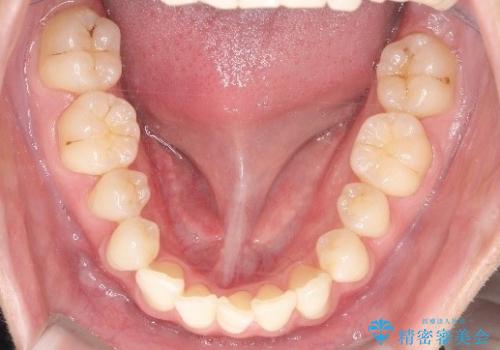

初診時の歯並びの状態としては、上下ともに前歯部の中等度のがたつきがあり、上の前歯が重なっている状態でした。

また元々下の前歯は1本少なく、歯の本数が少ないことを前提とした矯正治療を行いました。